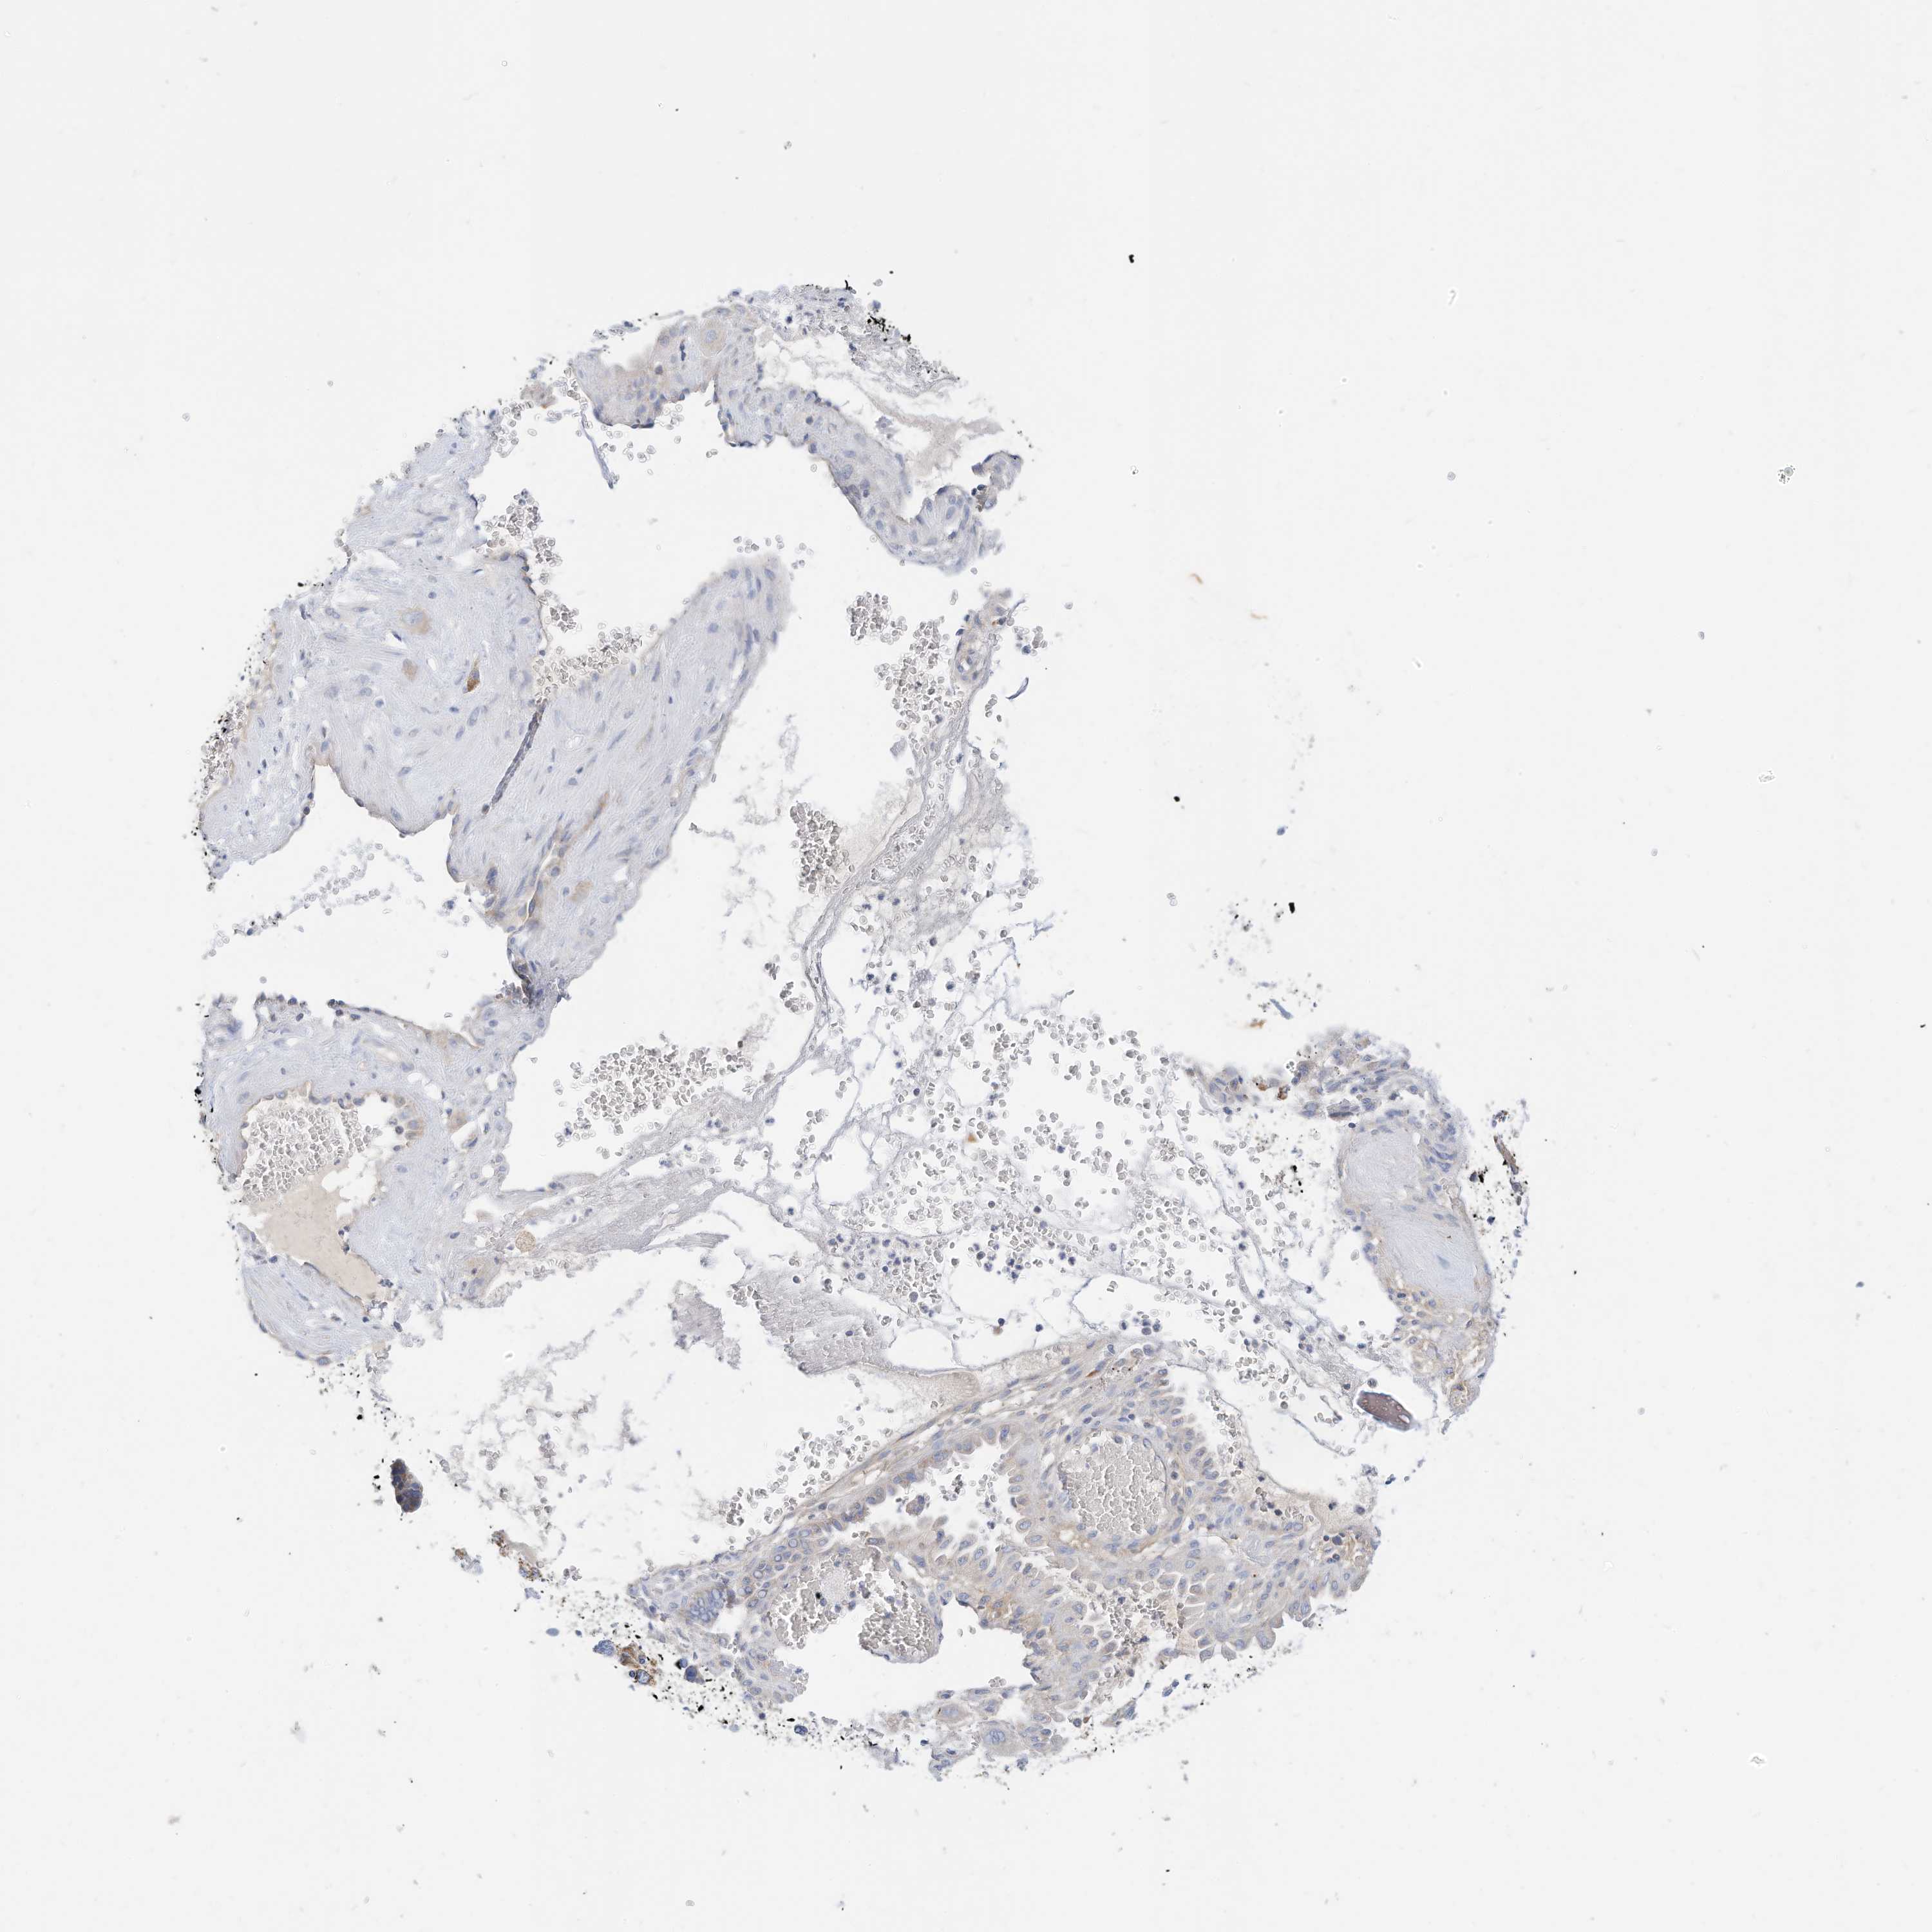

CERVICAL CANCER - Protein expressioni

A mouse-over function shows sample information and annotation data. Click on an image to view it in a full screen mode. Samples can be filtered based on level of antibody staining by selecting one or several of the following categories: high, medium, low and not detected. The assay and annotation is described here.

Note that samples used for immunohistochemistry by the Human Protein Atlas do not correspond to samples in the TCGA dataset.

Antibody stainingi

Antibody staining in the annotated cell types in the current human tissue is reported as not detected, low, medium, or high, based on conventional immunohistochemistry profiling in selected tissues. This score is based on the combination of the staining intensity and fraction of stained cells.

Each image is clickable and will lead to virtual microscopy that enables deeper exploration of all samples and also displays staining intensity scores, fraction scores and subcellular localization as well as patient and tissue information for each sample.

Antibody HPA030345

Squamous cell carcinoma, NOS

Adenocarcinoma, NOS